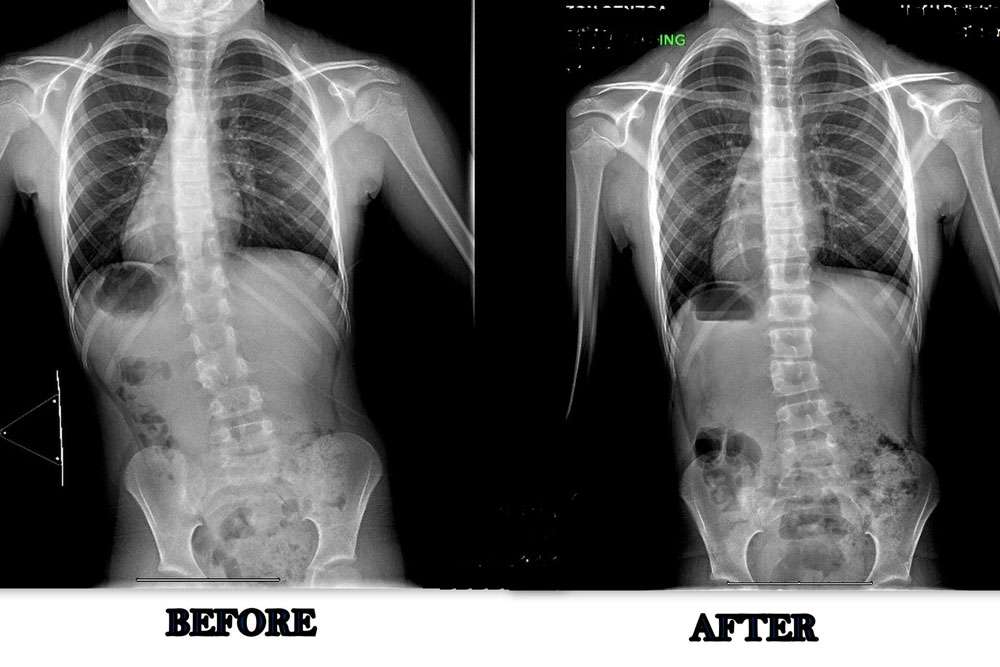

Scoliosis is measured on x-ray as a Cobb Angle. This measurement tells us how bad the scoliosis is and then guides us in how we treat it. Curves under 10 degrees usually aren’t considered scoliosis. Those curves 10-25 are called mild curves and we treat them with scoliosis specific exercise. Curves 25-45 degrees are treated with scoliosis specific exercise and bracing. Those above 45 degrees are usually surgical candidates. There is a measurement error of 3-5 degrees, which means to really have significant change, it needs to be above that.

Here are some examples of what can be done with scoliosis specific exercise with a variety of patients. The main goal of treatment is to STOP progression of the curve. With hard work and dedication we can also see reduction in the curve.